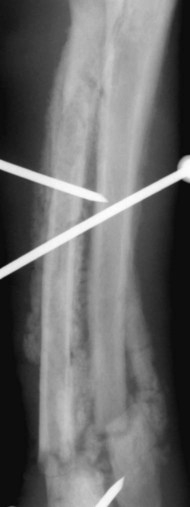

It is useful to note that it is the head of the non-fractured bone that is dislocated. DISTAL RADIUS FRACTURES Colles Fracture VS Smith Fracture t.me/MedNoteCollection - medicine medicalstudent doctor mednotecollection orthopedic. About Press Copyright Contact us Creators Advertise Developers Terms Privacy Policy & Safety How YouTube works Test new features NFL Sunday Ticket Press Copyright. Nondisplaced or minimally displaced fractures of the distal wrist, such as Colles and Smith fractures or greenstick, buckle, and physeal fractures in children carpal bone fractures other than. Wrist fracture in which the distal end of the radius is displaced forwards. The Smith’s fracture is a specific type of injury to the forearm bone (the radius) near the wrist joint.